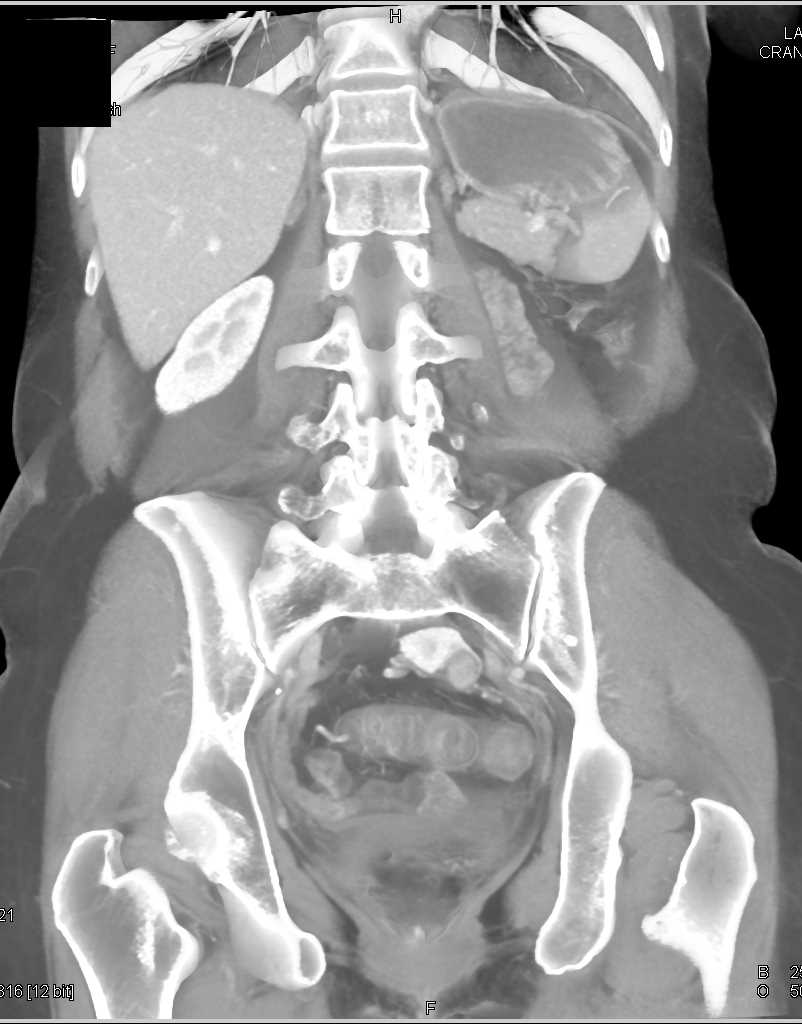

Renal Cell Carcinoma is a Solid Mass